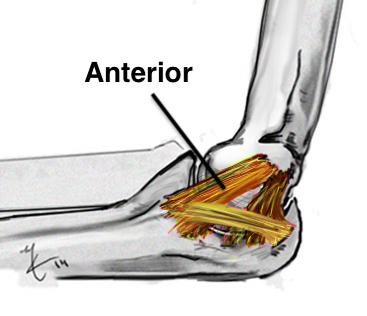

Anatomy of Ulna Collateral Ligament (UCL)

Provides valgus stability

Three components

| Anterior band | Posterior band | Transverse band |

Most important Stabilizes from 30 - 90 degrees flexion |

| Medial epicondyle to sublime tubercle |

Taut band Mean 6 mm thick |